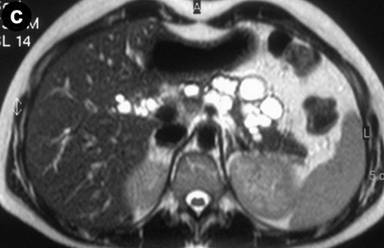

A 27-year-old female underwent a cholecystectomy for lithiasis. The patient was successively evaluated for diffuse and recurrent abdominal pain; no alcohol and/or smoking habits were reported. Laboratory measurements of total bilirubin and pancreatic amylases were unremarkable. Abdominal ultrasound was carried out which showed multiple hepatic and pancreatic cystic lesions; a dynamic enhanced CT scan confirmed the presence of multiple liver and pancreatic cystic lesions, but, in particular, the differentiation between simple hepatic cysts and cystic ectasia of the biliary ducts suggestive of Caroli’s disease was not reached. Therefore, MRI was requested to characterize the liver lesions and it was performed acquiring T1- and T2-weighted sequences integrated with T2-hydrographic images to specifically evaluate the biliary tract in axial and coronal views. MR cholangiography after intravenous administration of mangafodipir trisodium (Teslascan®, Nycomed, Amersham, Oslo, Norway), was also performed using T1-weighted sequences. Turbo spin echo T2-weighted images in axial and coronal views showed multiple hyperintense focal lesions in the left lobe of the liver, typical of cystic lesions, as well as multiple pancreatic cysts of the tail and saccular ectasia of the main biliary duct (Figure 1). T2-hydrographic dedicated images confirmed these findings, but certain imaging signs for a differential diagnosis between simple hepatic cysts and biliary cysts were not identified (Figure 2). However, the enhanced mangafodipir trisodium T1-weighted MRI clearly showed that some of the liver cysts concentrated mangafodipir trisodium contrast medium, thus demonstrating that these enhanced cystic lesions were in communication with the biliary ducts providing imaging criteria consistent with a diagnosis of Caroli’s disease (Figure 3). A segmental hepatectomy specimen demonstrated dilated simil-cystic intrahepatic ducts of the IV segment corresponding to a diagnosis of Caroli’s disease.

Figure 1. Conventional turbo spin echo T2-weighted axial (a., b. and c.) and coronal (d.) MR views show multiple cystic lesions in the left liver lobe as well as in the pancreatic tail. Saccular ectasia of the main biliary duct is also depicted. |